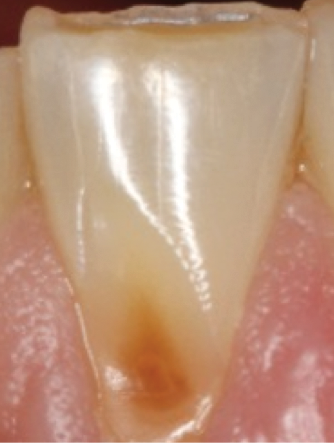

Translucency on the incisal edge of a tooth and intact gingival margin may indicate moderate erosion. In severe cases, the morphology of the tooth becomes significantly altered, which may lead to dentin and/or pulp exposure (Figure 4). The white translucent enamel becomes worn from the surface, leaving yellow dentin and reddish pulp. Worn incisal edges of teeth can be prone to further weakening and fractures. Exposed dentin can cause hypersensitivity to cold, hot, and tactile stimuli.21 If untreated, an exposed pulp may be susceptible to infection and necrosis.

Fig 4. Facial erosion with aggressive abrasion of maxillary anterior teeth. Note pulp exposure on facial surface of canine.

Figure 4